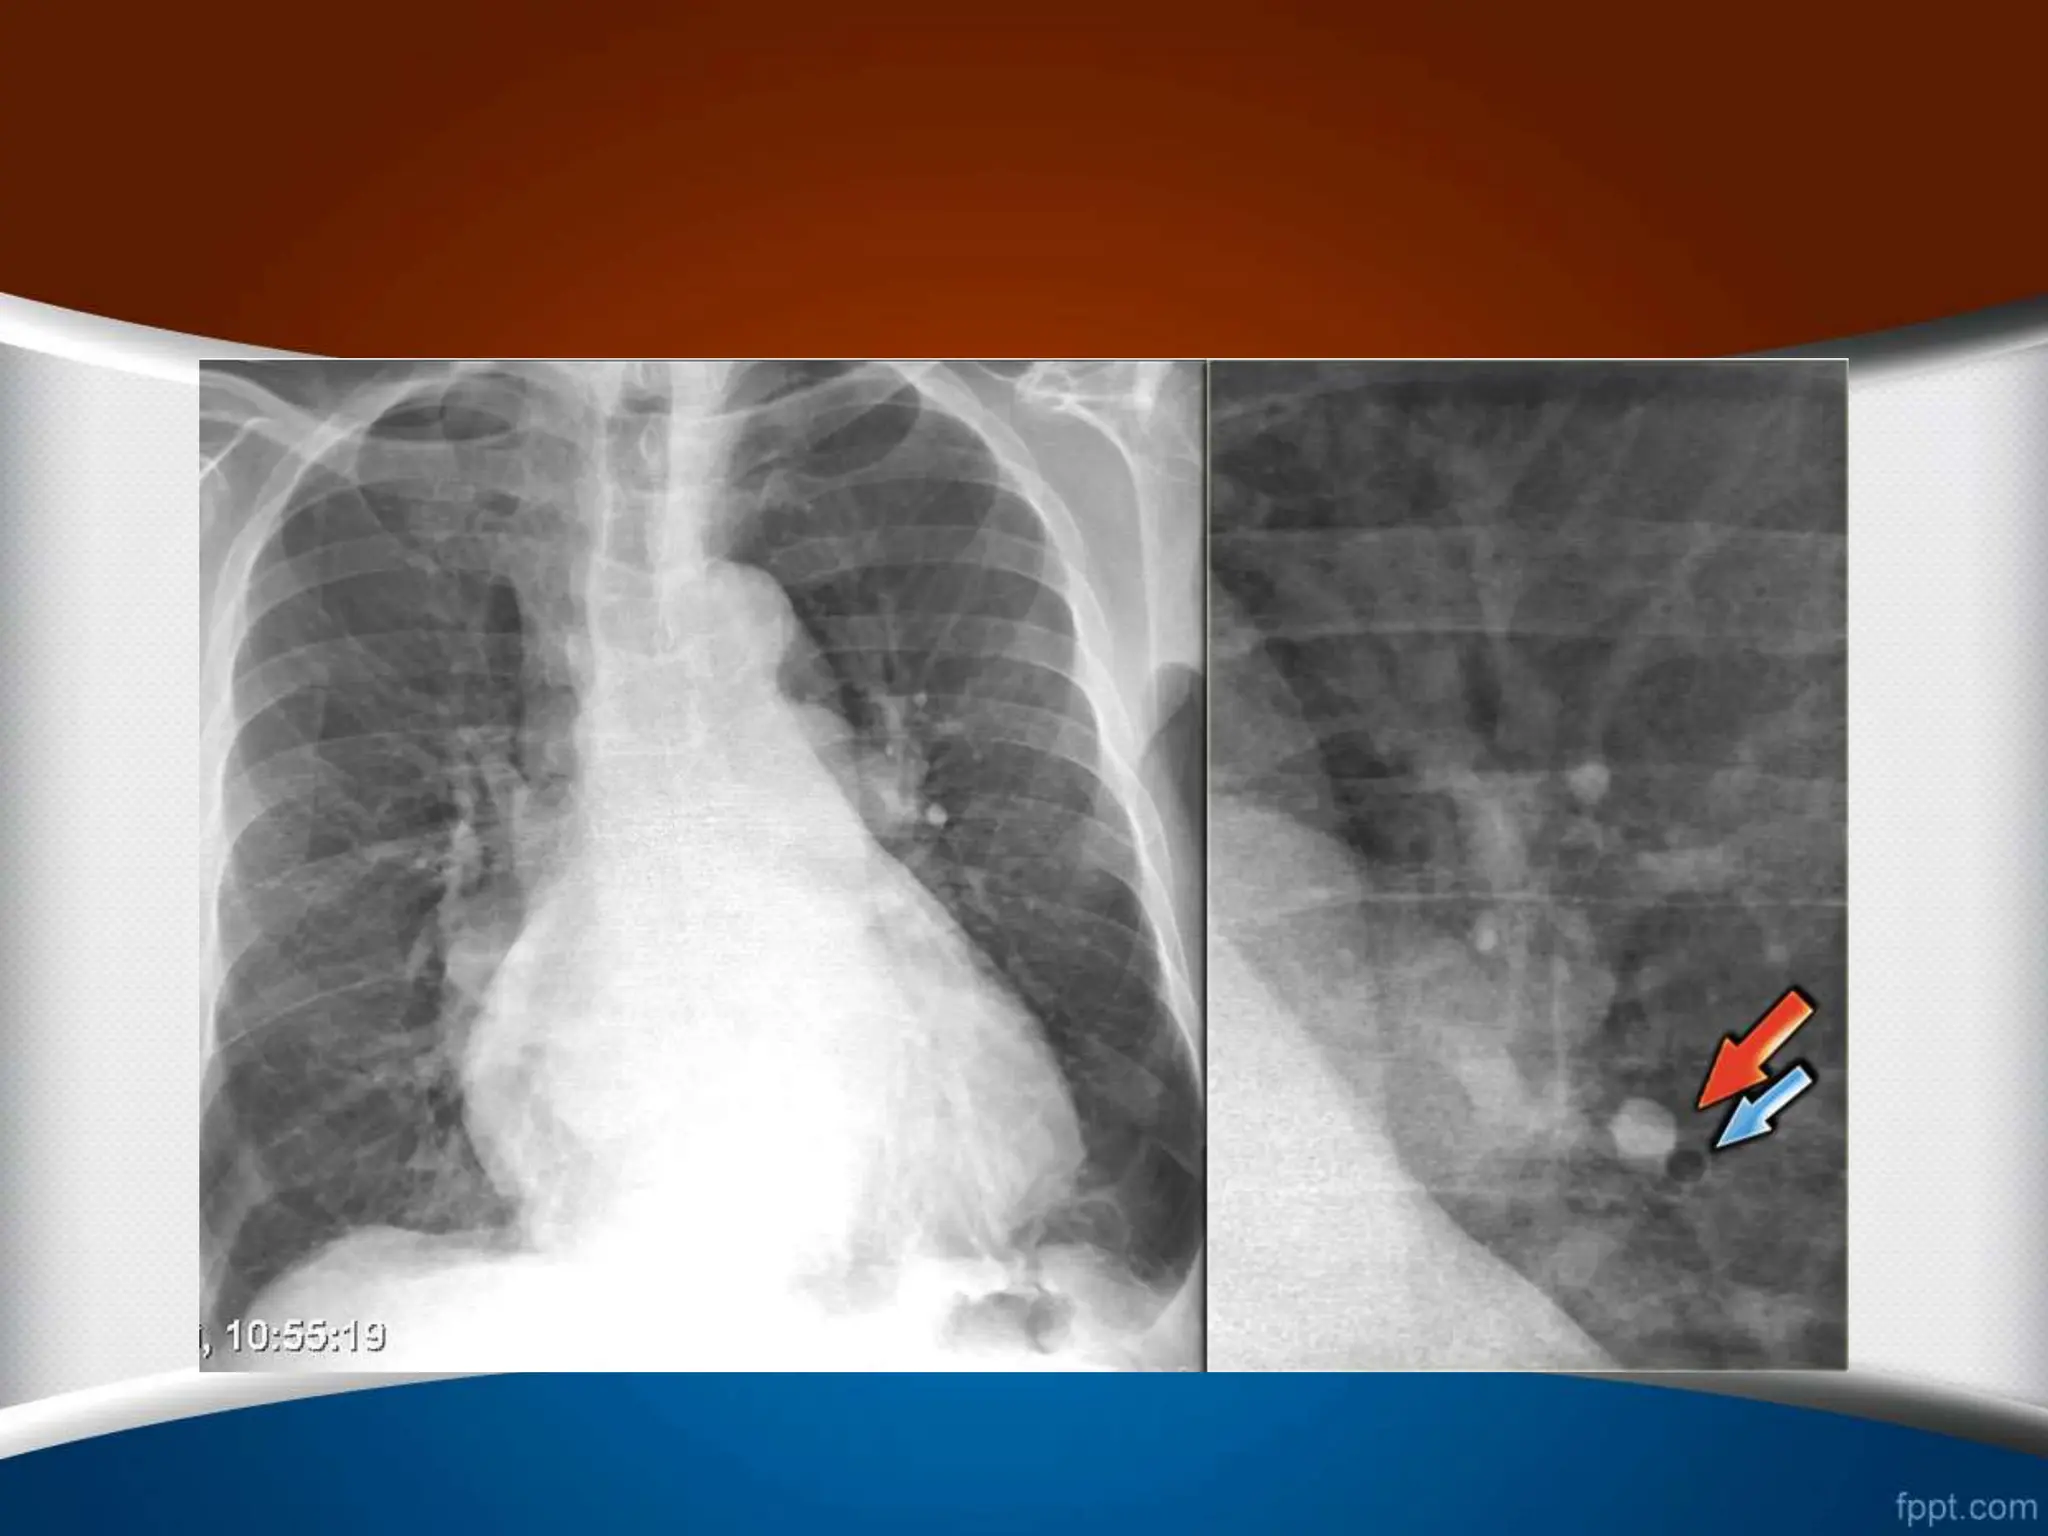

‫یا‬ ‫ریوی‬ ‫وریدی‬‫هیپرتانسیون‬ Post Capillary Pulmonary Hypertension - Pulmonary venous hyper tension 1 . ‫خون‬ ‫جریان‬ ‫مجدد‬ ‫توزیع‬ ‫اول‬ ‫مرحله‬ • ‫که‬ ‫حالتی‬ ‫در‬ Redistribution ‫نسبت‬ ‫دهد‬ ‫می‬ ‫رخ‬ A/B ‫ج‬ ‫بهترین‬ ‫و‬ ‫یابد‬ ‫می‬ ‫افزایش‬ ‫میانی‬ ‫و‬ ‫فوقانی‬ ‫لوب‬ ‫در‬ ‫برای‬ ‫ا‬ ‫است‬ ‫ریه‬ ‫ناف‬ ‫اطراف‬ ‫ی‬ ‫ناحیه‬ ‫آن‬ ‫ی‬ ‫مشاهده‬ . • ‫سفالیزاسیون‬

• #79 در گرافی سمت چپ، نسبت کاردیوتوراسیک افزایش یافته است. توزیع مجدد عروق ریوی دیده می شود ودر اطراف ناف ریه مقطع شریان (فلش قرمز) از مقطع برونش (فلش آبی) بیشتر است.